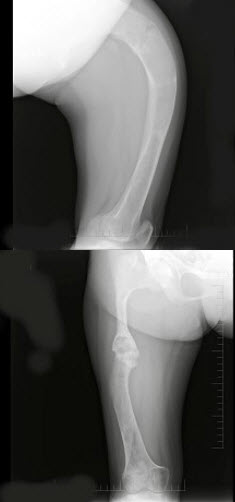

75、单项选择题

男,60岁,左股骨痛1年余,结合图像,最可能的诊断是()

A.骨纤维异常增殖症

B.Paget病

C.髋关节结核

D.股骨头缺血坏死

E.化脓性骨髓炎

77、单项选择题

男,17岁,下肢畸形,有皮肤色素沉着,性早熟等,结合图像,最可能的诊断是()

A.非骨化性纤维瘤

B.骨巨细胞瘤

C.骨纤维结构不良

D.内生软骨瘤

E.畸形性骨炎